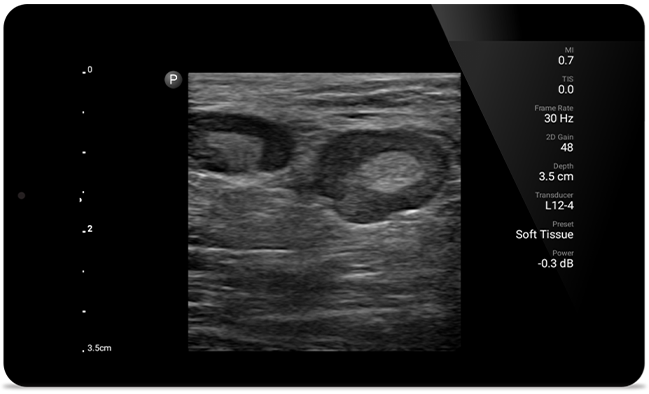

Lumify L12-4 broadband linear array transducer

• 12 to 4 MHz extended operating frequency range

• Aperture size: 34mm

• 2D, steerable color Doppler, M-mode, advancedXRES and multivariate harmonic imaging, SonoCT

• High resolution imaging for shallow applications: soft tissue, vascular, superficial, musculoskeletal and lung

• Center line marker

• USB-C transducer with replaceable cable